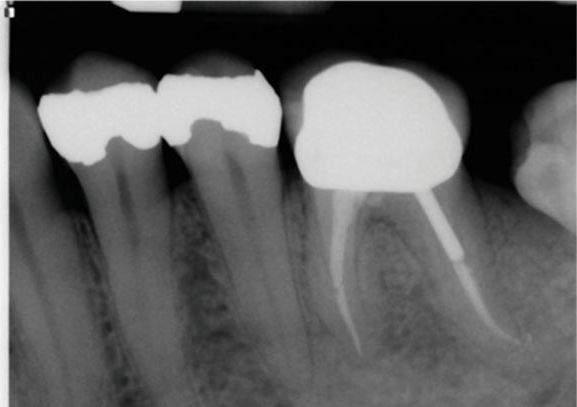

(1.) Preoperative radiograph of teeth Nos. 30 and 31 exhibiting previously treated, symptomatic apical periodontitis and pulp necrosis with a chronic apical abscess and an endodontic-periodontic lesion, respectively.

Figure 1

(2.) Postoperative radiograph after the performance of nonsurgical root canal re-treatment on tooth No. 30 and root canal therapy with hydraulic condensation and bioceramic sealer on both teeth followed by amalgam core buildups. (Case courtesy of David Tran, DMD, Advanced Graduate Program in Endodontics, Harvard School of Dental Medicine).

Figure 2